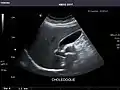

Gallbladder

Gallbladder: No stones, wall thickening, or pericholecystic fluid.